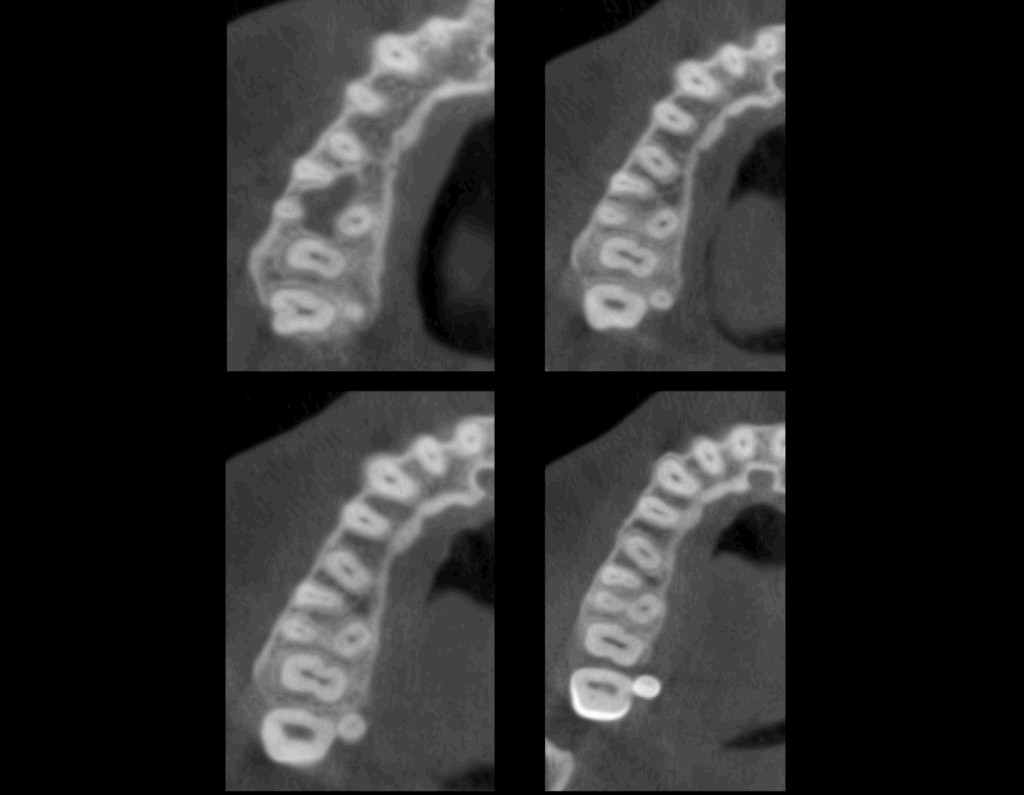

A la evaluación de la tomografía computarizada (en cortes axiales y transaxiales) se puede observar la presencia de una pieza supernumeraria de tamaño reducido (microdiente)localizada por lingual de la pieza 18 y que al evaluar los cortes tangenciales se aprecia una discreta dilaceración hacia distal.

CORTES AXIALES

CORTES TRANSAXIALES